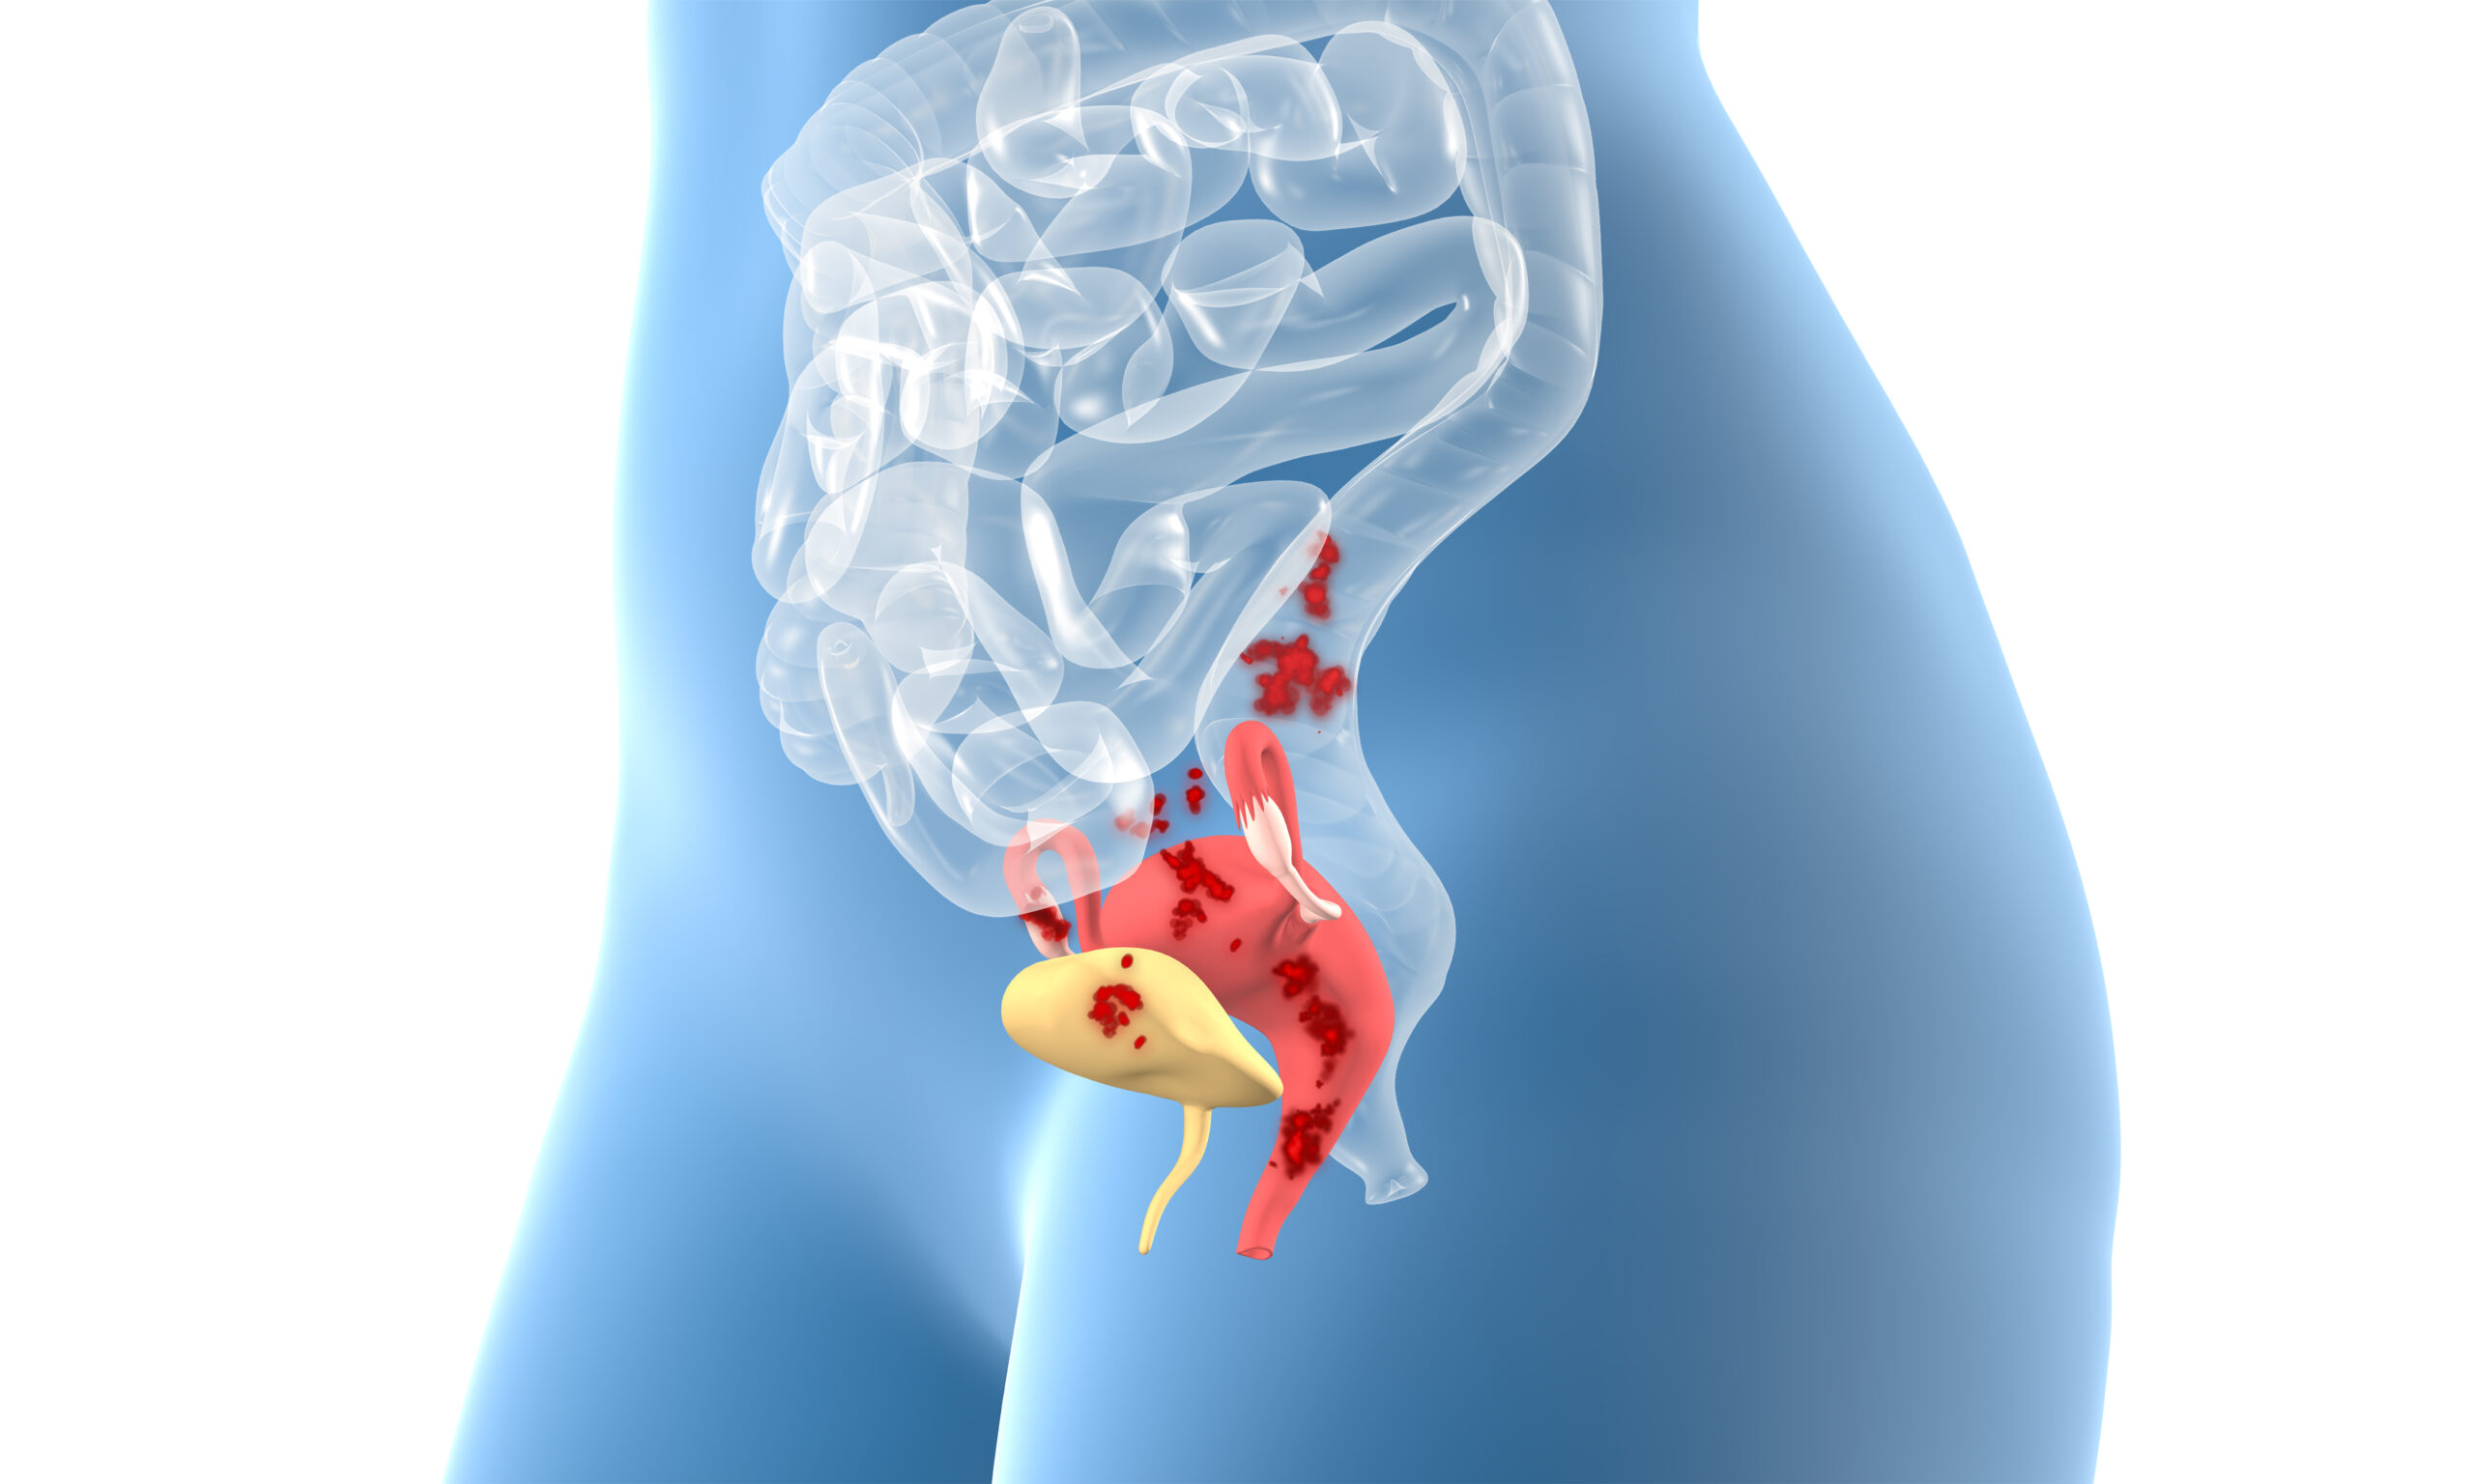

Endometriosis is a condition in which tissue similar to the lining of the uterus grows outside the uterus. These so-called endometrial lesions respond to the menstrual cycle, but cause inflammation, severe pain, and scarring because the blood cannot flow out naturally. These lesions can develop anywhere in the abdominal cavity—for example, on the ovaries, intestines, or bladder—and in rare cases, even outside of it, such as in the lungs.